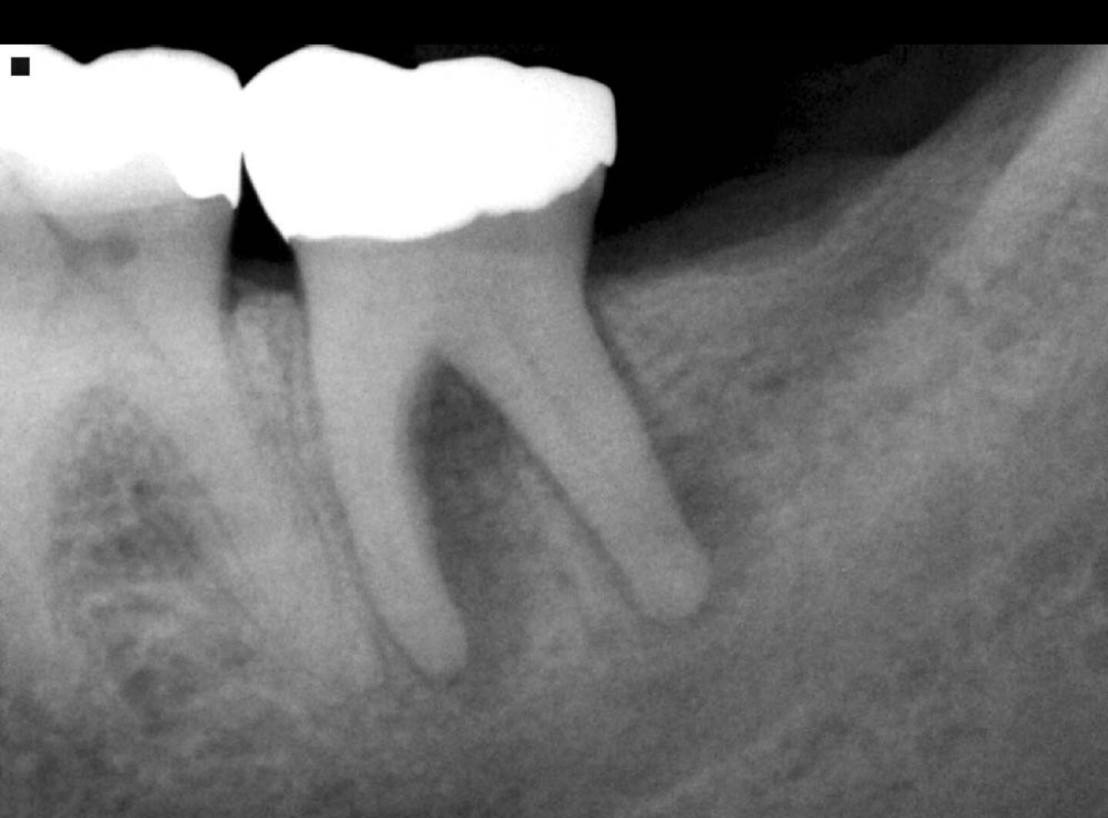

แสดงตัวอย่าง Case study